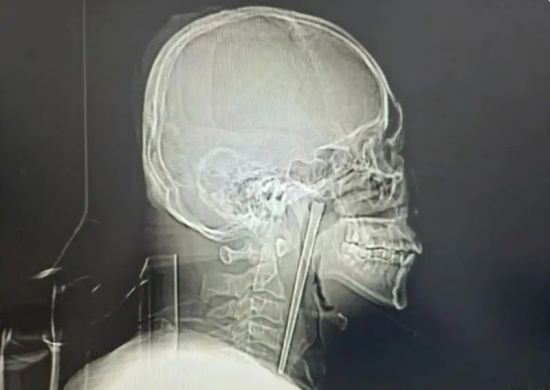

• 아시아경제"이게 8년 됐다고요?" 충격받은 의사…12cm 젓가락 삼키고 버틴 남성